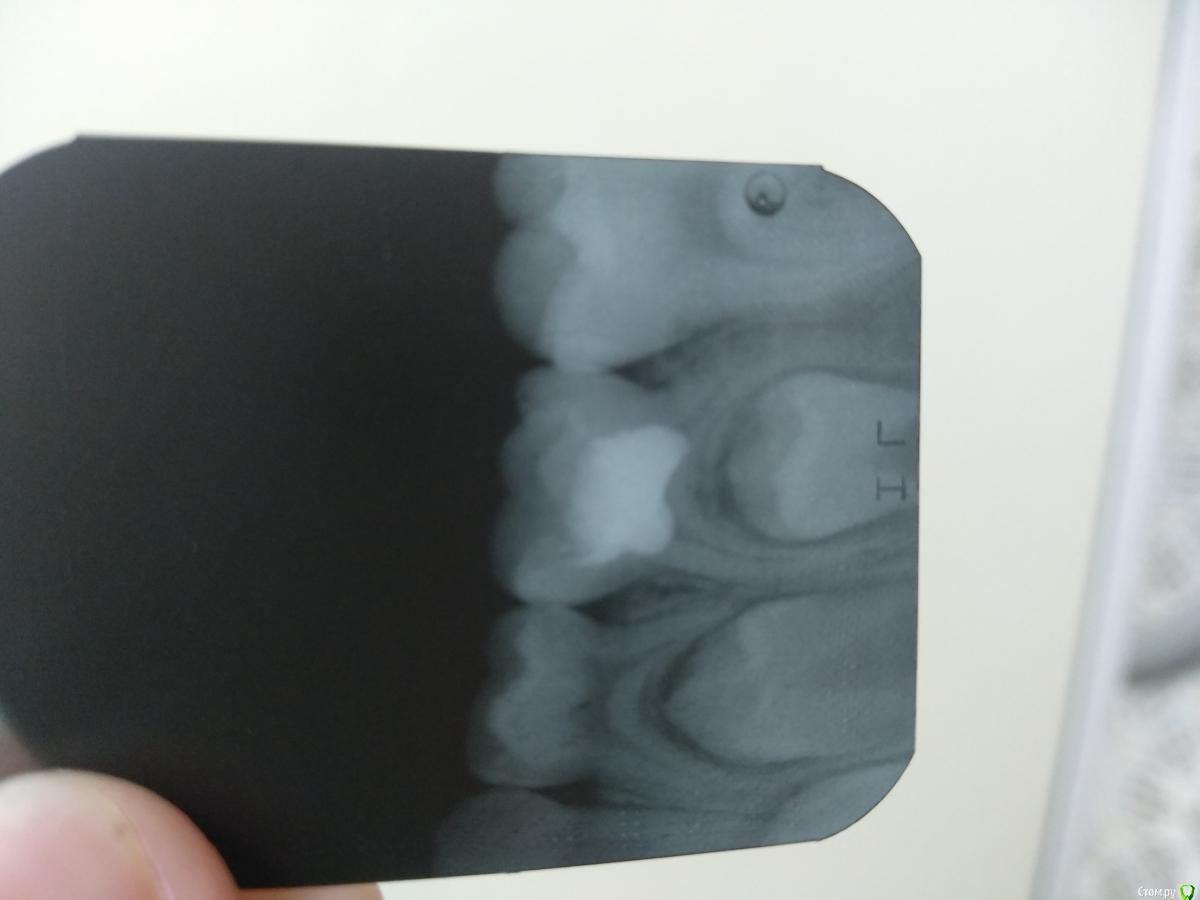

Катерина45045 Опубликовано 19 декабря, 2018 Поделиться Опубликовано 19 декабря, 2018 RG 85 1 Ссылка на комментарий

Катерина45045 Опубликовано 19 декабря, 2018 Поделиться Опубликовано 19 декабря, 2018 Решила начать лечить ампутационное в рамках ОМС.Витальная ампутация зуб 8.5. Препарирование,гемостаз,на устья ЦОЭ,прокладка фосфат-цемент,и пломба из ЭвикролаКак считаете это достойно? Не хочу делать РФ как всё,слишком много осложнений после него и ходить по 3 раза долго 1 Ссылка на комментарий